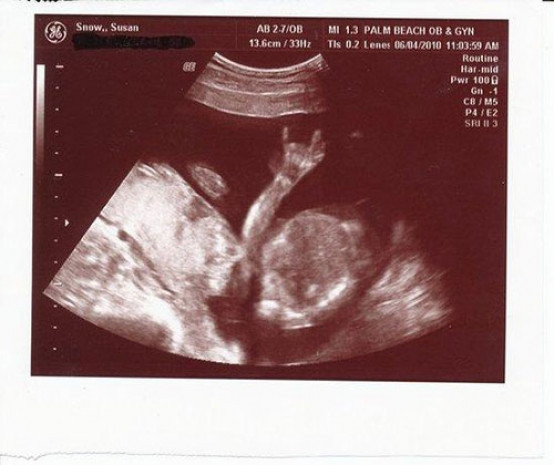

Ultrasonda gördüler dehşete düştüler doktor odadan kaçtı - Resim: 1

Anne baba olmanın ilk heyecanlarını yaşamak paha biçilemez. Hele birde ilk ultrasonda girilip, minik fetüsle tanışıldığı o an başka hiçbir ana değişilmez. Peki ya bebeğinizi ilk gördüğünüz an kaçacak delik arasınız? Evet bebeğiniz yerine garip bir şey görseniz ve korkunuzdan ne yapacağınızı şaşırsanız? Bunu yaşayanların sayısı hiç azımsanacak kadar değil.